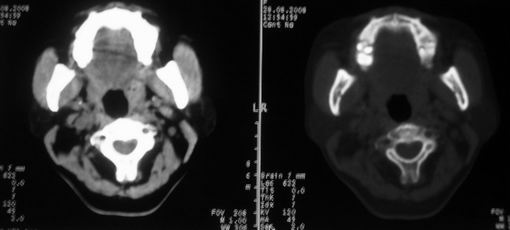

女,55岁,右侧颌下肿物3年。

右侧胸锁乳突肌后方软组织密度肿块,界限清楚。多考虑:血管源性肿瘤!

鼻咽左侧壁增厚,呈结节样突入鼻咽腔内,左侧咽隐窝消失,须考虑鼻咽癌可能,建议鼻咽纤维镜检查以明确诊断。

至于右侧颌下间隙的结节影,如果不考虑病史的话,可以诊断为淋巴结转移。但是结合病史“右侧颌下肿物3年”,又不象淋巴结转移了。建议ct增强扫描明确结节与右侧颌下腺的关系,或者穿刺活检定性。

右侧胸锁乳突肌内侧略低密度结节,应该是静内静脉而不是淋巴结。